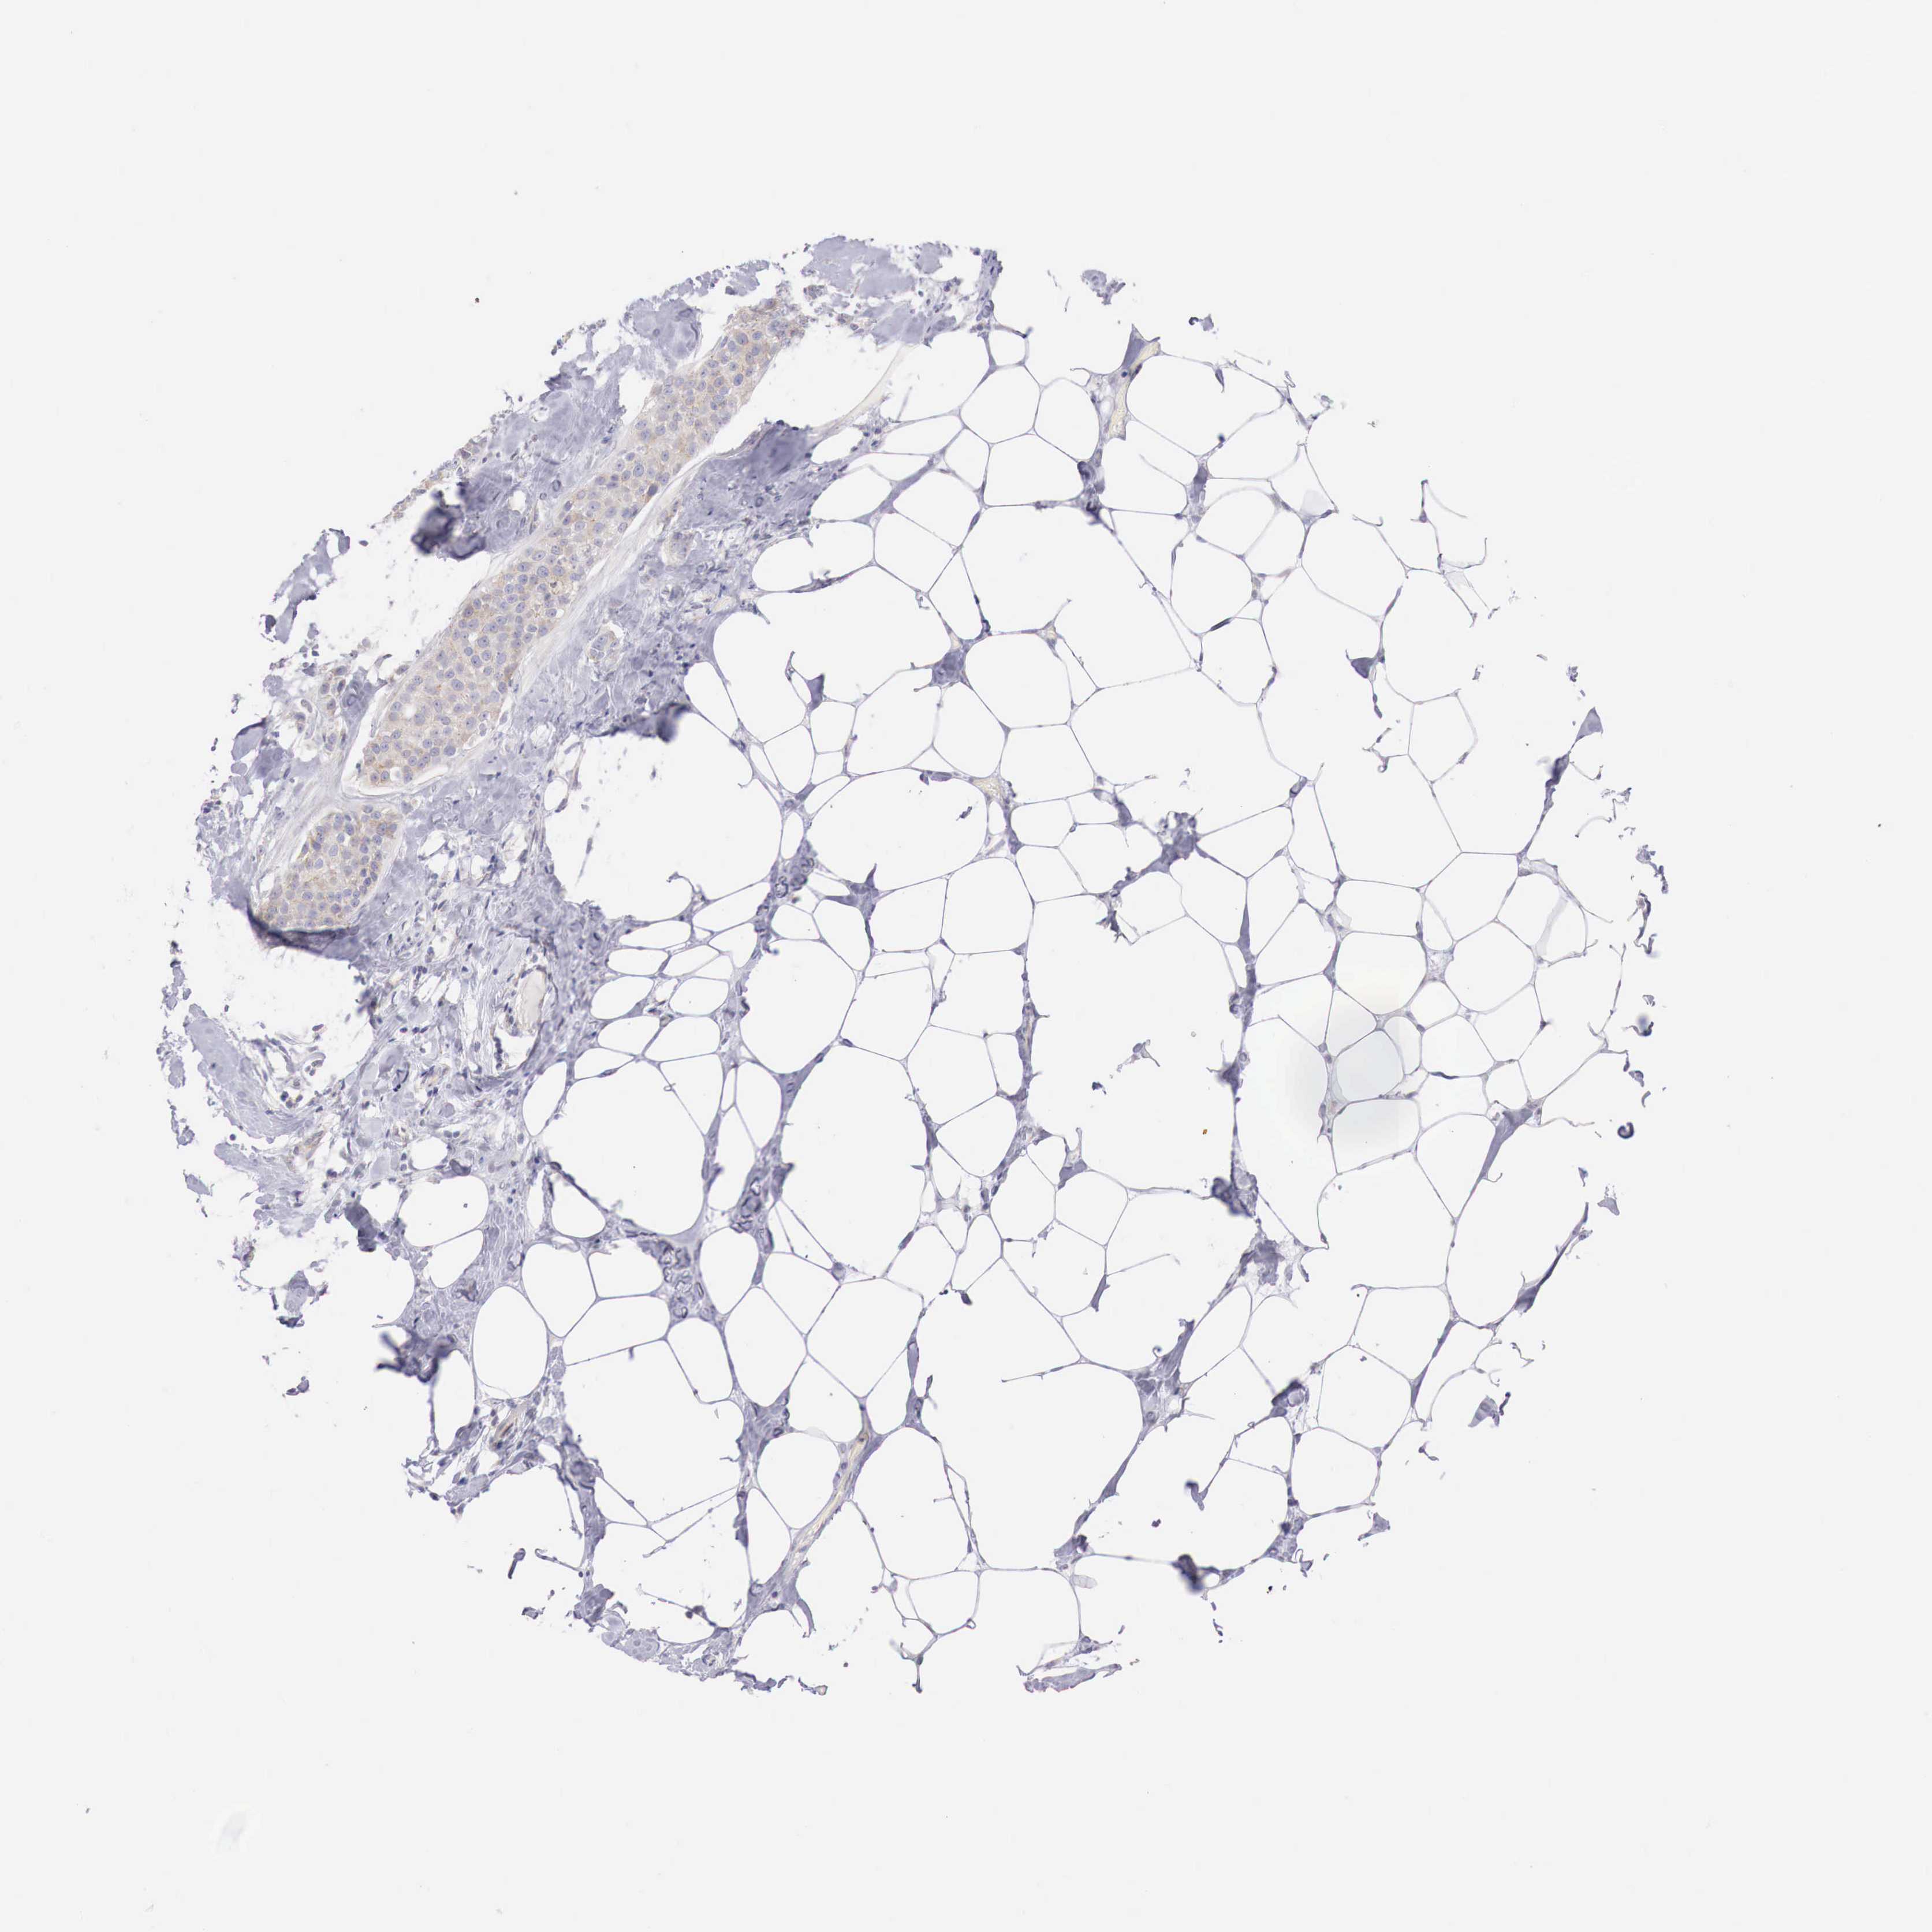

Breast cancer

Human cancer